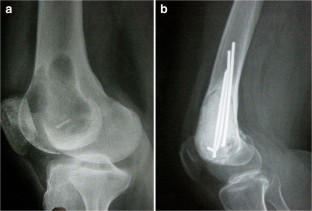

Fig. 1